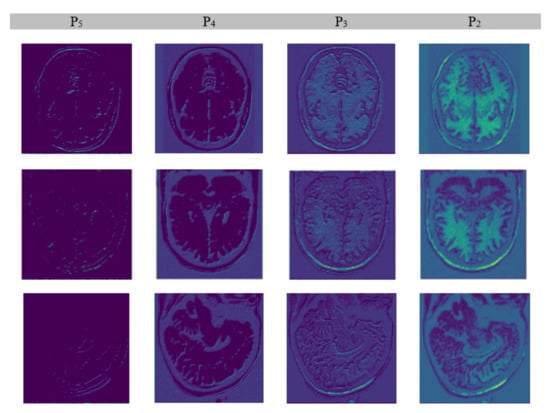

3.5. Extraction of Feature Maps

We extracted features from the input brain MR images by applying a convolutional neural network equipped with ResNet-101-FPN architecture. ResNet–101 comprises 101 convolutional layers wherein initial layers extract edges while terminal side layers extract brain regions. Moreover, terminal side layers also convert images into feature maps. The process works in a structure of three dimensions from the bottom to top, from the top down, and to horizons making it robust. The bottom-to-top dimension has convolutional layers from C1 to C5; the top-to-bottom dimension has layers from P2 to P5, while a horizontal connection of 3 × 3 kernel having a double effect (2×) of P* and C* exists in between both vertical dimensions. The refining of feature maps worked from P5 to P2. The inner-most layer (P2) created the best feature map. Figure 7 depicts the output of the feature extraction process.

Figure 7. Extraction of features.